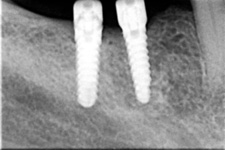

Podmínkou je opět dostatečné množství kosti.

Protetické řešení může být pomocí můstku, který je kotvený na implantátech nebo pomocí jednotlivých korunek na implantátech.